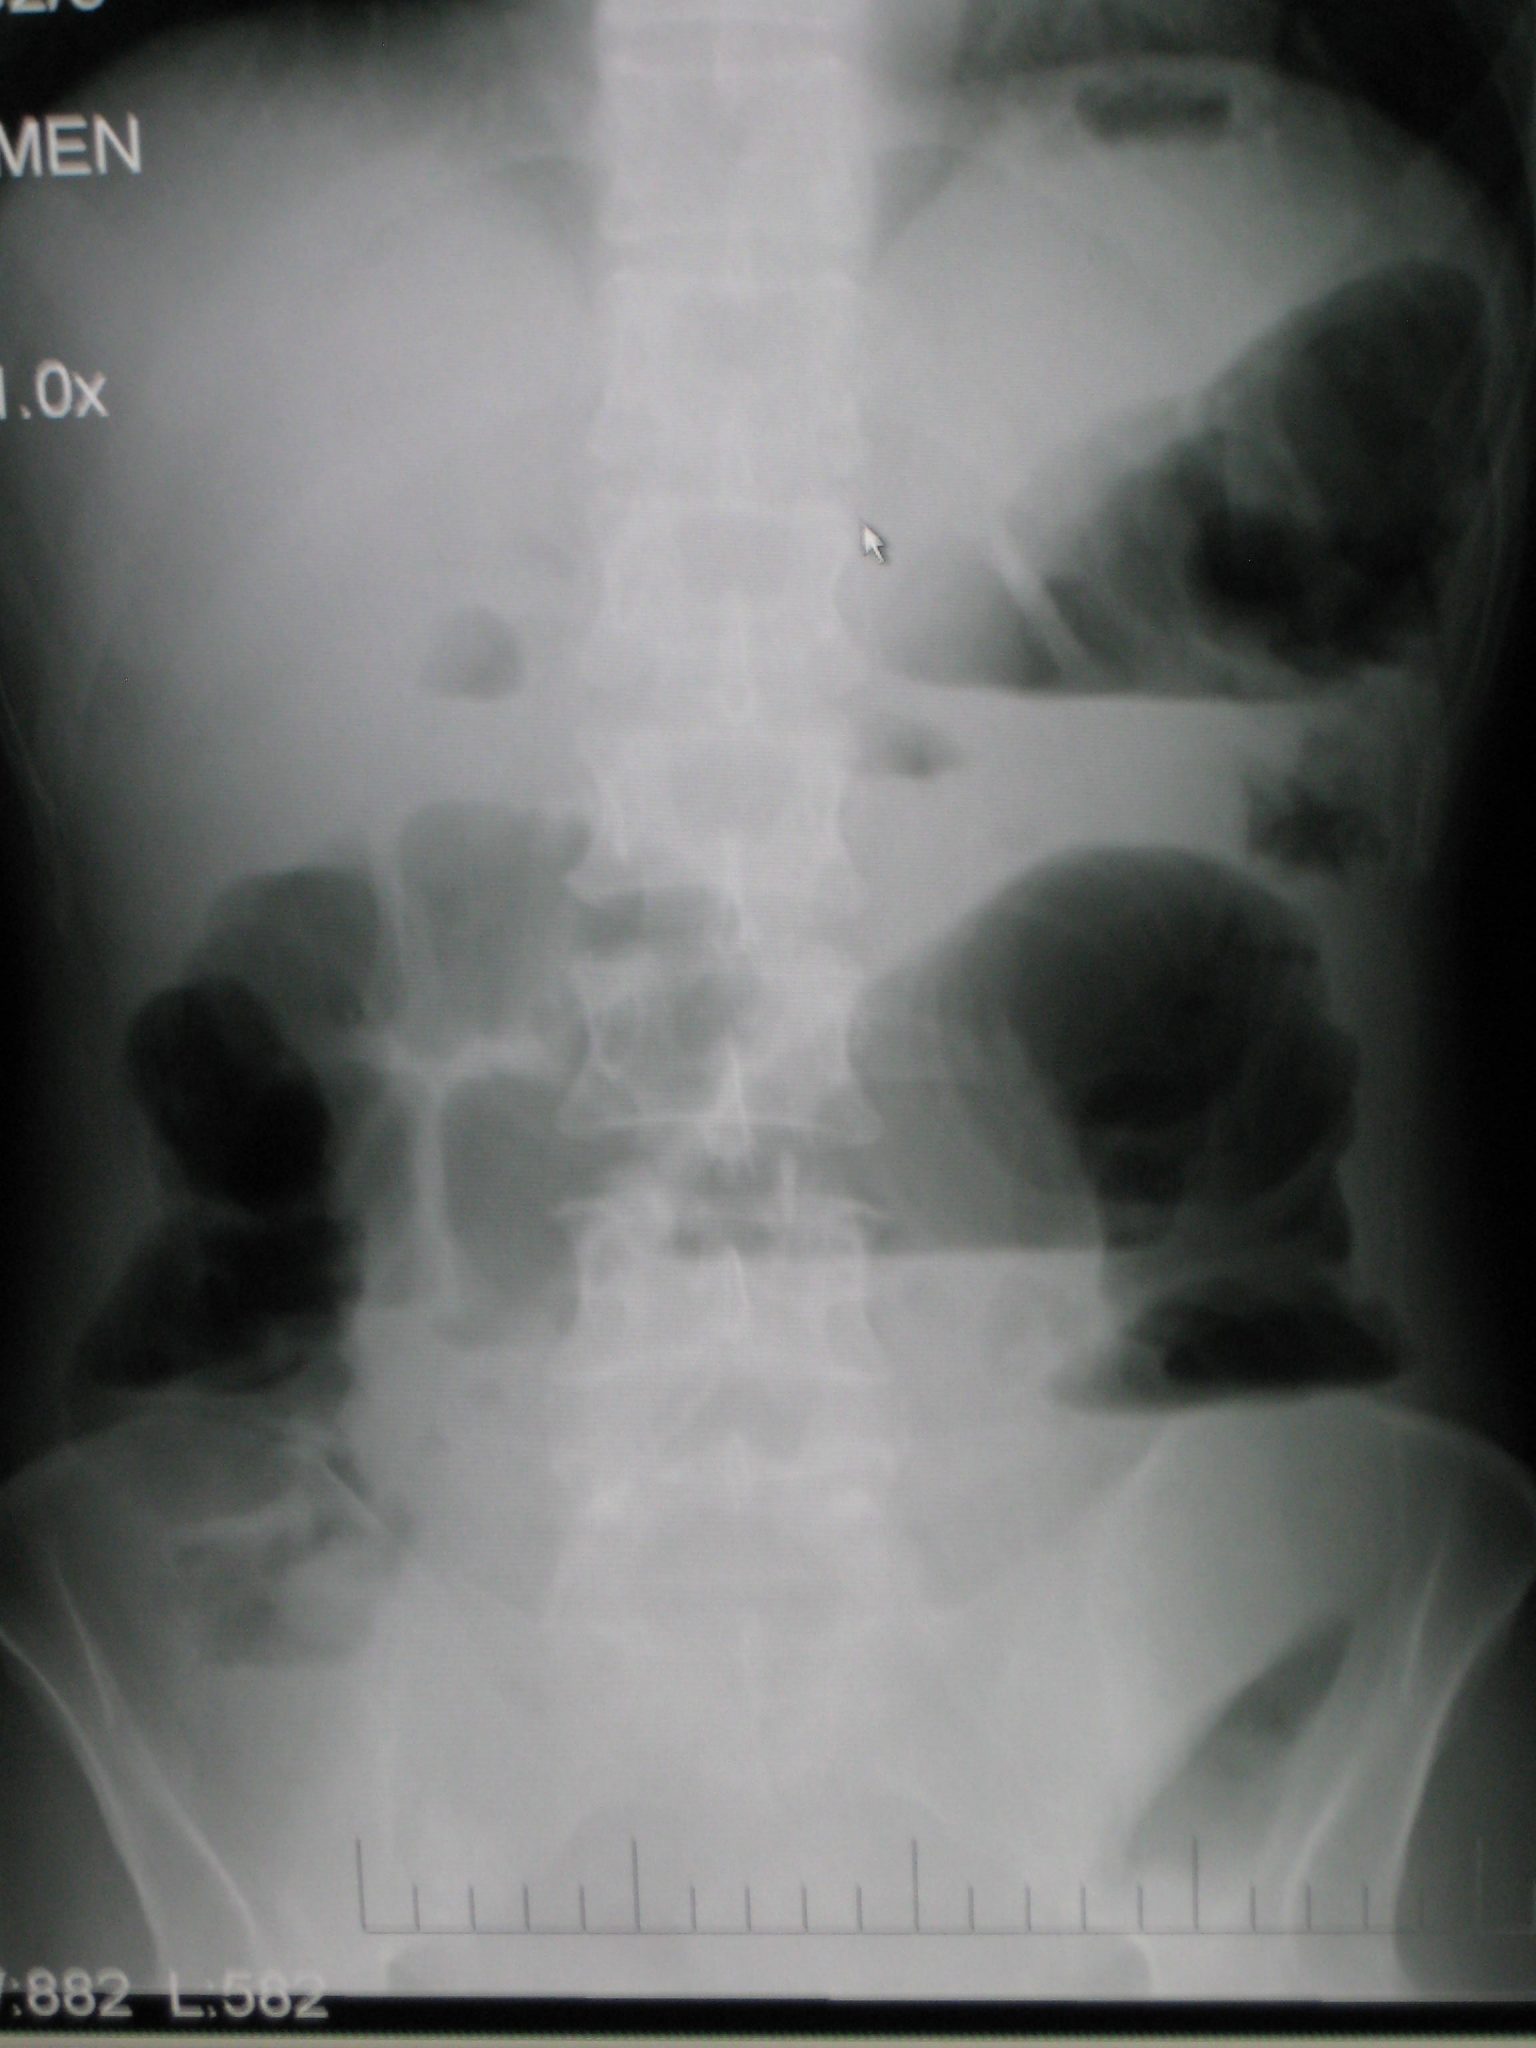

قد يكتشف الطبيب أثناء إجراء الفحص الجسدي وجود انتفاخ أو مضض tenderness أو فتوق في البطن. وتتضمن الفحوص التي تظهر الانسداد ما يلي:

- الصورة المقطعية المحوسبة للبطن.

- صورة البطن البسيطة.